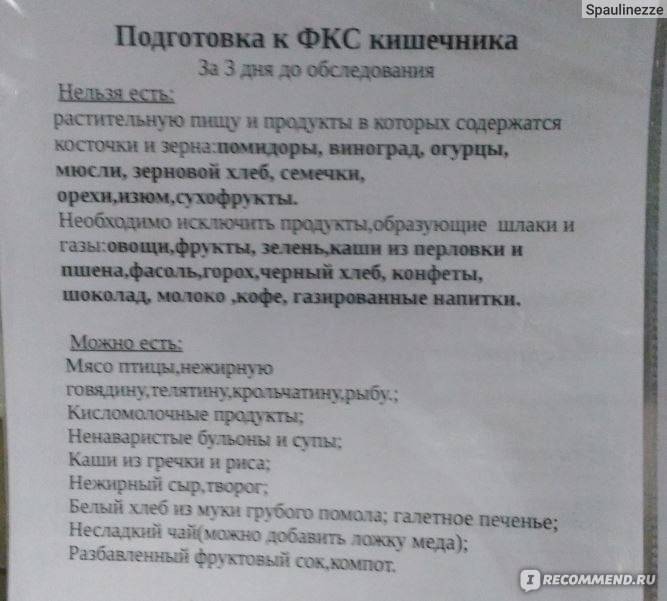

Подготовка к ирригоскопии: необходимые препараты